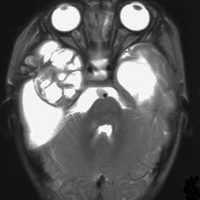

生後5ヶ月の女児に発生した右中頭蓋窩から海綿静脈洞から側頭下窩の成熟奇形腫です。腫瘍のう胞が大きく,右大脳半球の高度の圧排変形がみられます。

のう胞が巨大なので,まずのう胞腹腔シャントをして脳の変形を戻しました。その2ヶ月後に開頭手術で腫瘍を亜全摘出しています。

小児科から抗てんかん薬の投与を受けていますが学習障害などなくて正常です。また腫瘍再発もなく,看護学校へ通学しています。